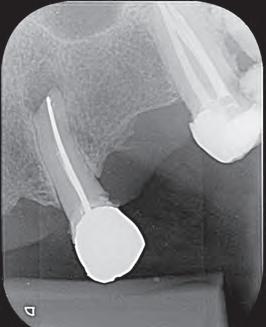

El retratamiento endodóntico del conducto obturado fue realizado con un enjuague final con EDTA 17% pasivamente activado ultrasonicamente, seguido por obturación del conducto radicular usando conos de gutapercha con BIO-C® REPAIR (Angelus - Brasil). BIO-C® REPAIR es un nuevo Cemento Endodóntico Biocerámico Listo para Uso. Puede ser colocado de la jeringa directamente al conducto radicular. Los conos de gutapercha fueron compactados con una técnica de compactación fría vertical (Figura 5).

Figura 5 - Obturación endodóntica

ambientes húmedos, inducción y conducción en la formación de tejidos duros, cementogénesis con consecuente formación de adherencia periodontal normal, hacen el material más adecuado para estas situaciones clínicas. En este caso, se utilizaron nuevos materiales biocerámicos para obturación de la cavidad retrógrada. En primer lugar, el BIO-C® REPAIR (Angelus - Brasil) se utilizó para obturar el espacio en el conducto radicular. Un tapón apical de BIO-C® REPAIR (Angelus - Brasil) fue colocado sobre la raíz, sellando la retro cavidad (Figura 10, Figura 11).

El seguimiento de 6 meses mostró una cicatrización ósea muy rápida. Clínicamente, ya no tenía signos ni síntomas de una enfermedad endodóntica (Figura 12). La cicatrización ósea rápida puede estar relacionada con la liberación de calcio de este nuevo material de reparación biocerámica que contiene tungstato de calcio como radiopacificador en lugar de Óxido de Bismuto de su antecesor (MTA convencional). Además, el tamaño de las partículas biocerámicas son menores que del MTA, permitiendo más contacto con los tejidos circundantes, aumentando la respuesta biológica.